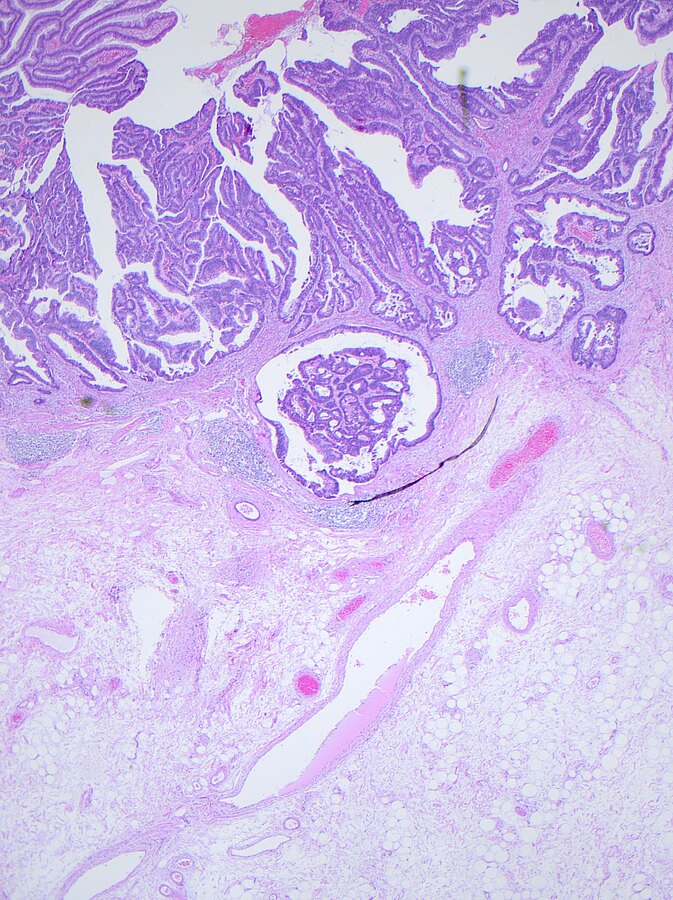

Je früher, desto besser. „Wenn wir den Darmkrebs in seinem ersten Stadium erkennen, können wir statistisch gesehen neun von zehn Patienten heilen“, sagt Privatdozent Dr. Steffen Mühldorfer, Chefarzt der Klinik für Gastroenterologie und Leiter des Darmzentrums. Doch noch immer ist Darmkrebs die zweithäufigste Krebstodesursache in Deutschland. Nach Angaben des Robert-Koch-Instituts sterben daran jährlich mehr als 25.000 Menschen. Mühldorfer rät deshalb zur Vorsorge. Jährlich sollten Patienten ab 50 ihren Stuhl auf Blutspuren untersuchen lassen. In absehbarer Zukunft wird sich das Analyseverfahren verbessern. Ein immunologischer Test soll zuverlässigere Ergebnisse liefern. Doch der Chefarzt sagt auch: Selbst der beste Test kommt nur etwa 60 Prozent der Darmkrebsfälle auf die Spur. „Mit Hilfe von Vorsorgekoloskopien, also von Darmspiegelungen, wäre ein Durchbruch möglich. Denn damit lässt sich die Krebsrate um bis zu 90 Prozent senken.“ Bei einer Darmspiegelung erkennen und entfernen Mediziner Polypen – sie sind die Vorstufe eines Karzinoms. Bereits seit 2002 übernehmen Krankenkassen für Patienten ab dem vollendeten 55. Lebensjahr die Kosten für eine Darmspiegelung.  Doch in den Jahren zwischen 2002 und 2012 haben pro Jahr nur 400.000 von insgesamt 16,7 Millionen Versicherten, die einen Anspruch auf eine Darmspiegelung hatten, tatsächlich davon Gebrauch gemacht. Der Anteil bei den Frauen liegt bei 22, bei den Männern bei 20 Prozent. „Ich rate jedem Anspruchsberechtigtem zu einer Darmspiegelung. Und wenn die abgelehnt wird zumindest zu einem Stuhltest “, sagt Mühldorfer.  Denn je früher Darmkrebs erkannt wird, desto besser die Heilungschancen.

Privatdozent Dr. Steffen Mühldorfer rät zur Darmspiegelung als wirksamste Vorsorgemethode gegen Darmkrebs.